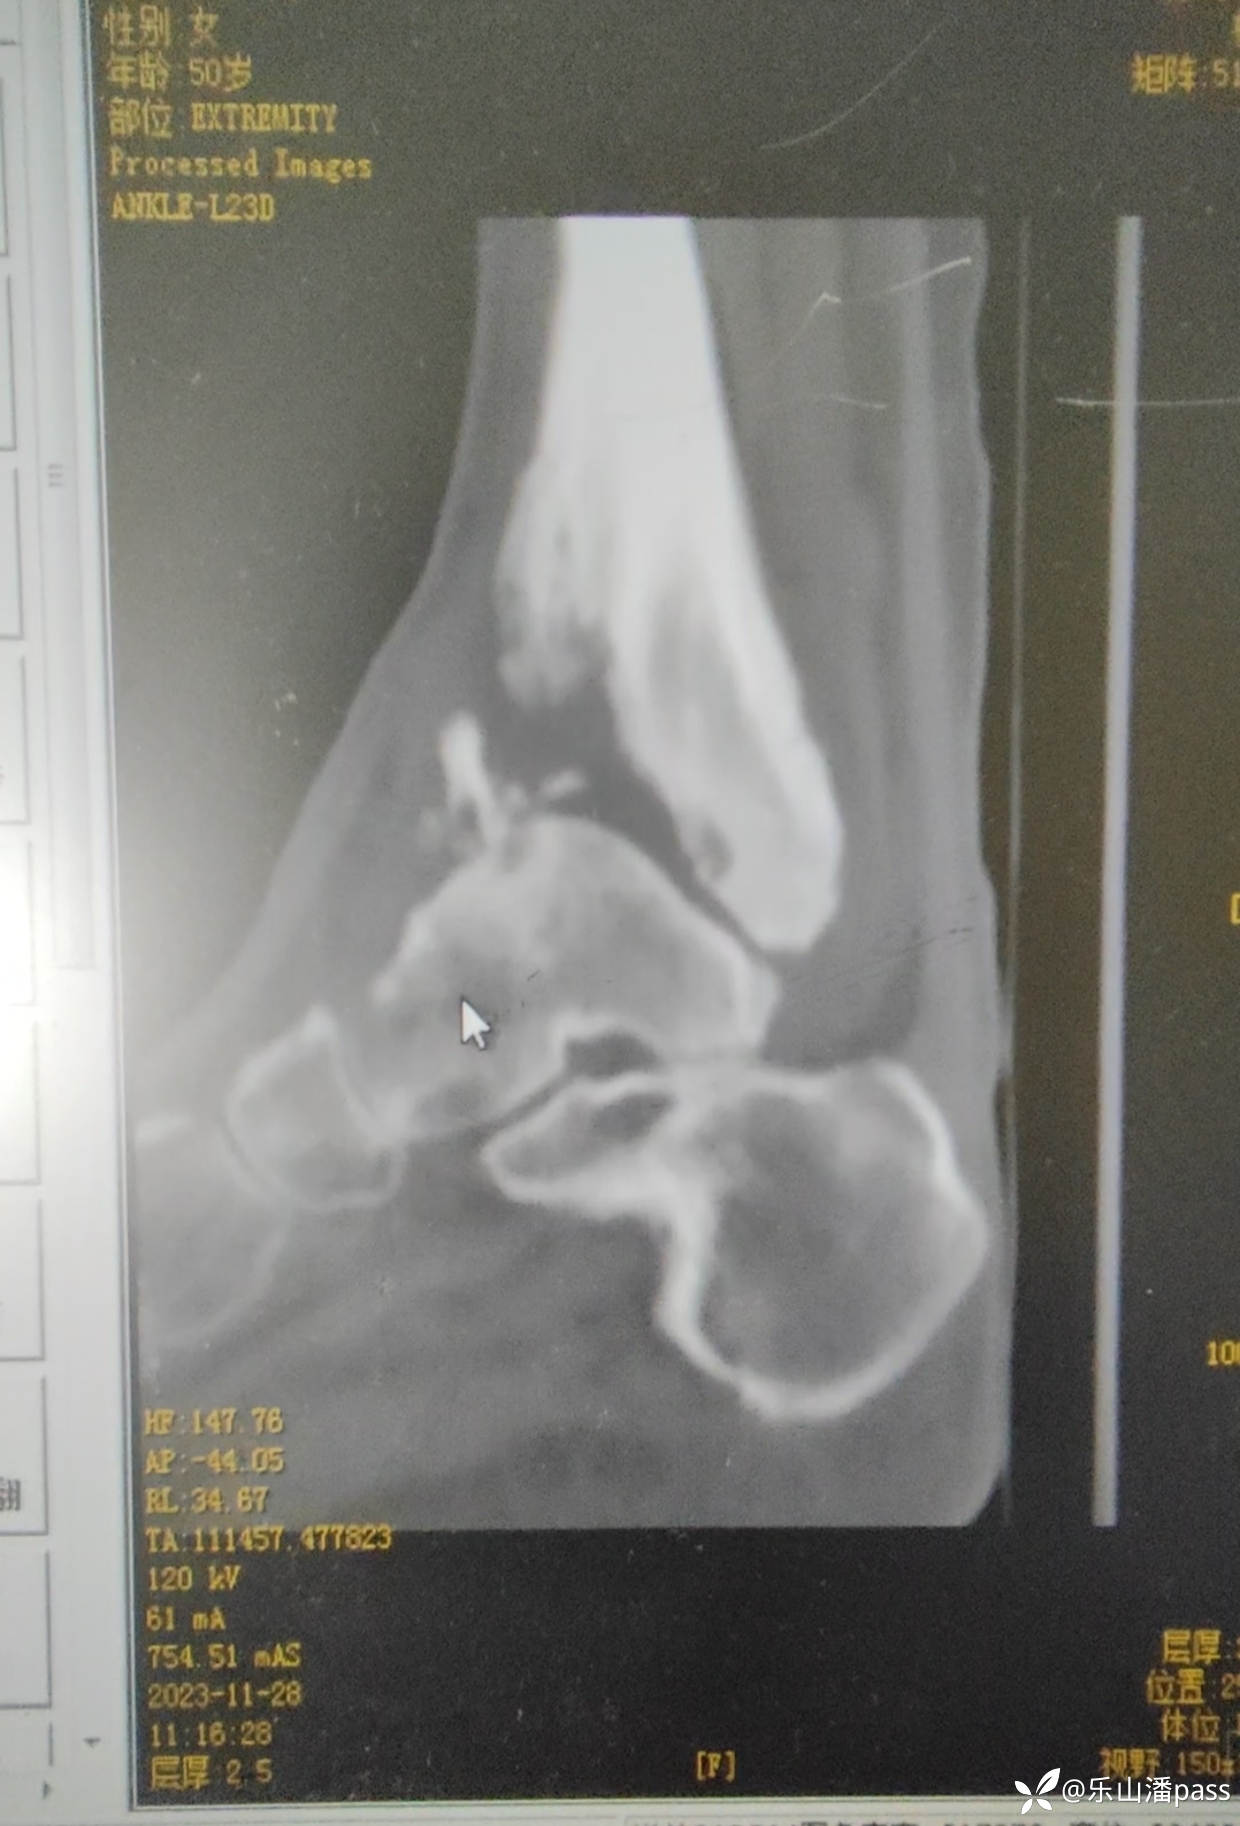

完善检查,排除感染等情况

img